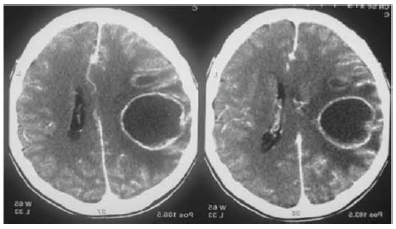

Um paciente de 32 anos de idade deu entrada no pronto-socorro com quadro de tosse e dor torácica de padrão pleural há cerca de um mês. Seu acompanhante refere que, há cinco dias, ele evoluiu com febre associada à cefaleia e, hoje, iniciou sonolência, afasia e hemiplegia à direita. O plantonista solicitou exames laboratoriais gerais, bem como tomografia computadorizada de crânio sem e com contraste. Após o resultado do exame de imagem mostrado a seguir, solicitou avaliação da neurocirurgia.